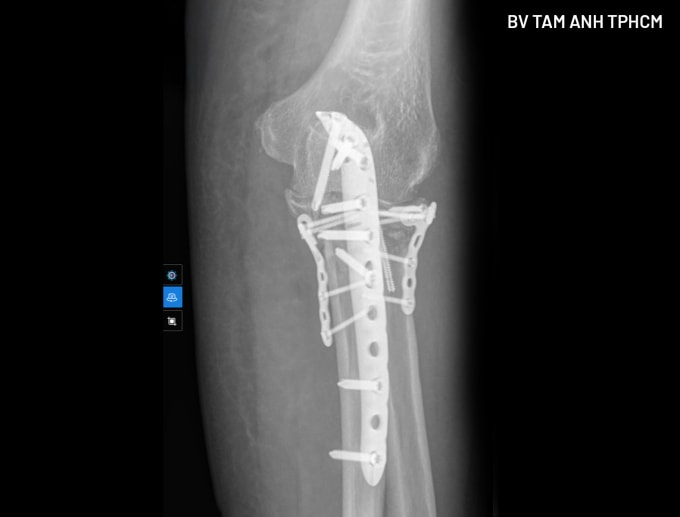

Kết quả chụp X-quang và CT tại Bệnh viện Đa khoa Tâm Anh TP HCM cho thấy đầu trên xương quay và xương trụ tay trái của bà Lợi gãy rất phức tạp. Theo BS.CKI Nguyễn Văn Thạnh, Trung tâm Chấn thương Chỉnh, phẫu thuật là phương pháp duy nhất giúp người bệnh hết đau và khôi phục vận động. Song người bệnh có nguy cơ cao biến chứng cứng khớp nếu không phục hồi được giải phẫu mặt khớp và cố định vững chắc. Vùng này còn có nhiều cấu trúc thần kinh, mạch máu và dây chằng quan trọng, dễ bị tổn thương trong quá trình phẫu thuật. Bà Lợi mắc nhiều bệnh nền, đặc biệt nhiễm trùng tiểu và tiểu đường hơn 20 năm không được kiểm soát tốt, có nguy cơ nhiễm trùng trong và sau phẫu thuật, chậm lành vết thương.

Để an toàn cho ca mổ, bác sĩ điều trị nội khoa cho bà Lợi trong 5 ngày, ổn định các chỉ số. Khi phẫu thuật, bác sĩ tiếp cận ổ gãy chỉ bằng một đường mổ duy nhất, từ phía sau, nắn chỉnh cả xương quay và xương trụ (mỏm khuỷu phía sau và mỏm vẹt phía trước) về đúng vị trí, sử dụng vít và nẹp để cố định, phục hồi giải phẫu hoàn toàn. Phương pháp này giúp giảm tối đa mất máu và tổn thương thần kinh mạch máu, các mô mềm khác. Người bệnh phục hồi nhanh hơn và giảm nguy cơ xảy ra biến chứng.